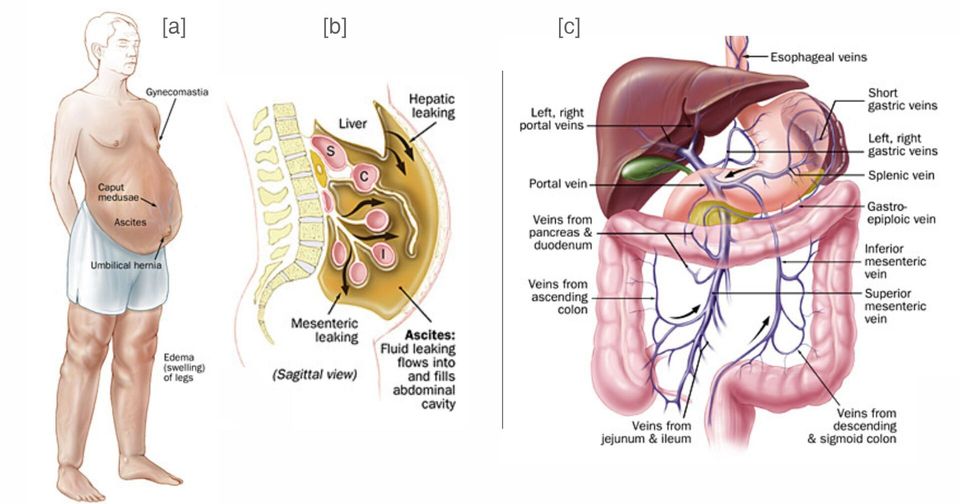

Portal Hypertension Symptoms Diagnosis And Treatment

Portal Hypertension Symptoms Diagnosis And Treatment

Portal Hypertension Symptoms Diagnosis And Treatment